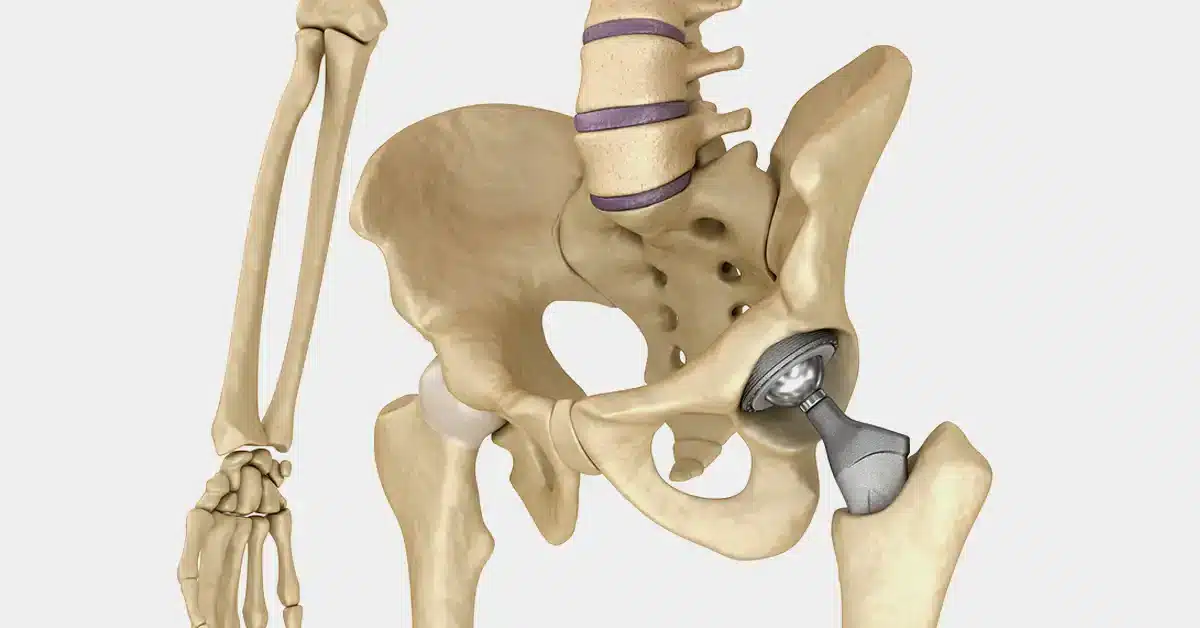

تعویض مفصل لگن

جراحی تعویض مفصل لگن، یکی از موفق آمیزترین روش های جراحی است که با هدف تسکین درد و بهبود دامنه حرکتی بیمار انجام می شود ...